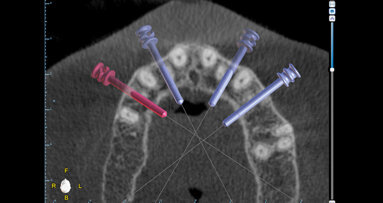

Fixní rekonstrukce celého oblouku nesené implantáty vyžadují správnou diagnostiku a plánování léčby. Jen tak je možno zhodnotit stávající ...